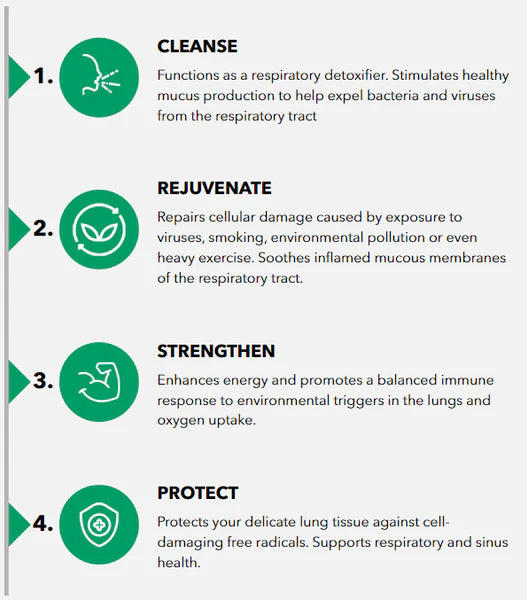

Amazing Health Benefits of Fivfivgo™: